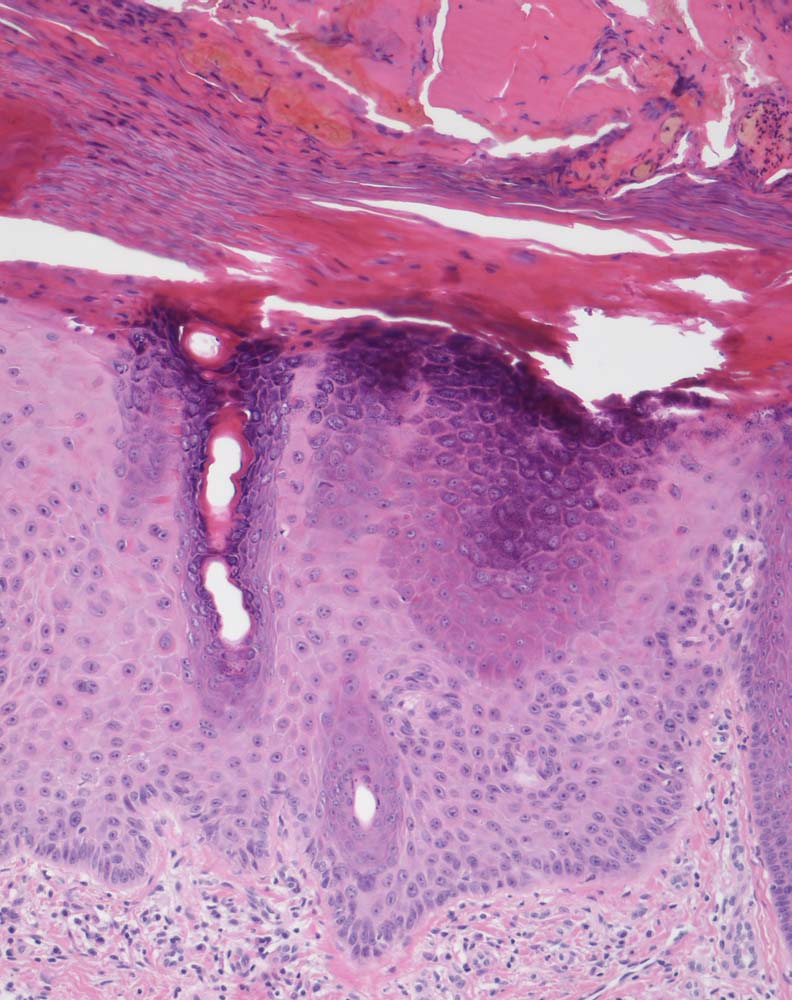

PathoPic – image database / PathoPic ID 9307 - Solare Präkanzerose (Keratose) hyperkeratotischer Typ

Solare Präkanzerose (Keratose) hyperkeratotischer Typ

Haut, Hand palmar, Finger

Hyper-parakeratotisch verhornende akanthotisch verbreiterte Epidermis mit Serokruste nach mechanischer Irritation. Abblassung und Atypien des Plattenepithels (vergrösserte hyperchromatische Kerne) in den basalen Abschnitten. Die Hautadnexe sind von den dyplastischen Veränderungen ausgespart.

Basalzellkarzinom rechtes Daumensattelgelenk.

Histologie

100